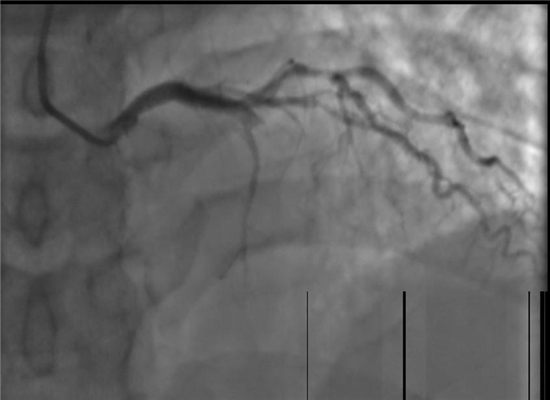

手术之前

在向患者家属详细说明手术的必要性及风险并征得同意后,杨勇主任带领科室介入手术团队迅速展开工作,将患者送入了导管室,并以最快的速度完善术前准备。23:02分开始手术,介入团队密切配合,快速穿刺桡动脉、置管、造影、开通闭塞血管,植入支架。经过约40分钟的全力救治,成功挽救了患者的生命。目前,术后患者症状明显改善,恢复较好。